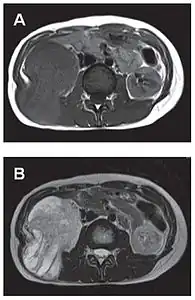

- Tumeur fibreuse solitaire du rétropéritoine

Aspect IRM, en séquence T1 (A) et T2 (B)[44].

L'imagerie par résonance magnétique permet une exploration complémentaire dans certaines localisations. Elle est surtout réalisée pour les tumeurs du système nerveux central[8],[12],[43], du foie et du pelvis[31],[41]. Elle évalue mieux les différences de densité intra-tumorale et permet d'affirmer l'absence d'envahissement des tissus mous et des structures osseuses voisines[20]. Les tumeurs fibreuses solitaires ont un aspect d'isosignal en séquence T1 et d'hypersignal en T2, et se rehaussent après l'injection de gadolinium[31]. Cependant, dans le système nerveux central, elles ne présentent pas de critères caractéristiques permettant de poser un diagnostic de manière uniquement radiologique[12] et, en pré-opératoire, sont souvent confondues avec un méningiome[43].